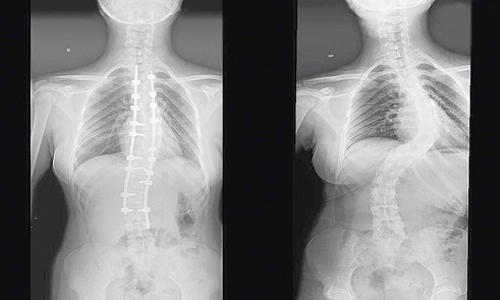

وقال الدكتور واصف السباعي استشاري جراحة العظام والعمود الفقري الحاصل على الزمالة البريطانية رئيس الفريق المعالج. فور وصول المريضة للمستشفى تم إخضاعها للفحوصات المخبرية وأشعة الرنين المغناطيسي على كامل منطقة الظهر، حيث أكدت النتائج وجود اعوجاج شديد يبلغ زاويته (78) درجة في الجهة اليسرى بالعمود الفقري مع تحدب وتشوه في القفص الصدري. مؤكداً على أن المريضة عانت لسنوات طويلة من المرض دون علاج الأمر الذي تسبب في زيادة شدة الانحناء والأعراض المصاحبة له.

وقد قرر الفريق الطبي بعد دراسة ملف المريضة التدخل الجراحي، وتبين أثناء العملية أن عظام الفتاة من النوع «الرخامي» النادر جداً، الذي عادة ما يكون شديد الصلابة ويحتاج تجهيزات وأدوات خاصة لتعديل العمود الفقري وتقوميه، بالإضافة إلى جهد ووقت أكثر أثناء العملية. موضحاً أن الجراحة استغرقت 6 ساعات متواصلة، تمكن خلالها الفريق الطبي وبفضل من الله من تقويم العمود الفقري وتثبيت ودمج الفقرات بشكل ممتاز. وقال استشاري جراحة العظام والعمود الفقري إن جهود الفريق الطبي تكللت بالنجاح ولله الحمد، إذ استطاعت الفتاة الوقوف بعد 24 ساعة من العملية، وقد تم إخضاعها لبرنامج علاج طبيعي مكثف لتقوية عضلات الظهر والفقرات. كما نصح الدكتور واصف السباعي جميع الحالات المشابهة التي تعاني من بداية الجنف بسرعة المتابعة الدورية مع الأطباء المختصين منذ اكتشاف الانحناء للحيلولة دون الإصابة بمزيد من المضاعفات وزيادة نسبة الجنف وبالتالي صعوبة علاجه.